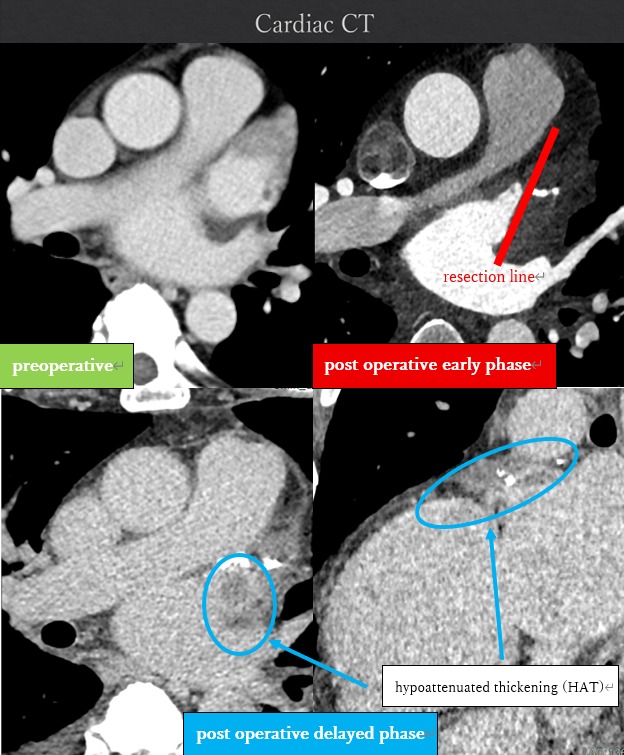

The patient had reduced left ventricular function, and tachycardia-induced cardiomyopathy was initially suspected. We therefore aimed for early restoration of sinus rhythm. Despite treatment with rivaroxaban, the patient developed a cardioembolic stroke, and a thrombus persisted in the LAA. Anticoagulation was switched to warfarin. During stroke rehabilitation and optimization of cardioprotective therapy, we monitored the thrombus for resolution, but it remained unchanged. Because an LAA occlusion device cannot be used in the presence of an existing thrombus, and thoracoscopic LAA resection is feasible when the thrombus does not extend to the LAA base, we decided to perform thoracoscopic LAA resection on hospital day 70. Intraoperative transesophageal echocardiography confirmed the absence of thrombus at the LAA base before resection. A thrombus was found within resected LAA specimen. However, postoperative computed tomography on hospital day 79 revealed hypoattenuated thickening (HAT) at the resection stump, suggestive of thrombus formation. Transesophageal echocardiography confirmed this finding. After intensifying warfarin management, the thrombus resolved approximately 20 days later. Catheter ablation was subsequently performed on hospital day 115, and the patient has since maintained sinus rhythm.